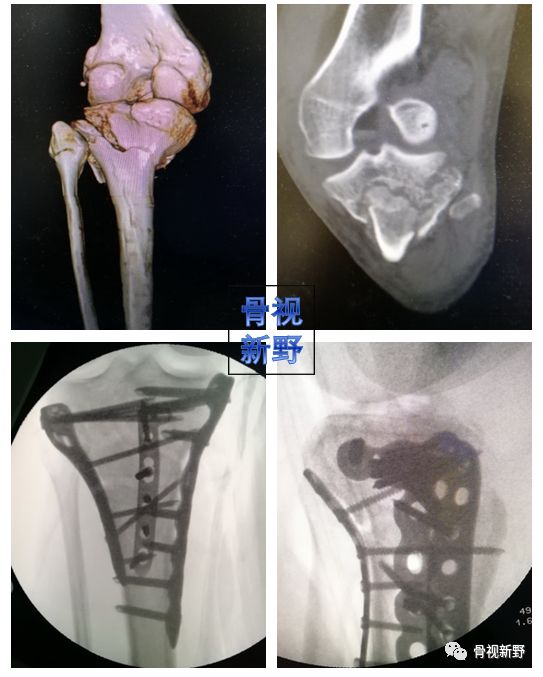

胫骨平台骨折的buttress固定

按照三柱理论,胫骨平台可分为外侧柱、内侧柱、后柱(后外、后内)。胫骨平台后柱骨折(尤其屈膝损伤者),由于骨折块存在较大的垂直剪力,往往需要buttress钢板作防滑固定,以对抗骨折块向下滑移的剪切力。

后外侧柱buttress钢板(Knee. 2018 Apr 17. pii: S0968-0160(18)30140-6)

三柱buttress钢板

除后柱骨折需要buttress钢板固定外,内、外侧平台塌陷、劈裂骨折常规所使用的钢板其实也是一种支持钢板。因此,笔者认为,胫骨平台骨折的内、外、后三柱均是buttress钢板的固定原理,防滑或支撑。